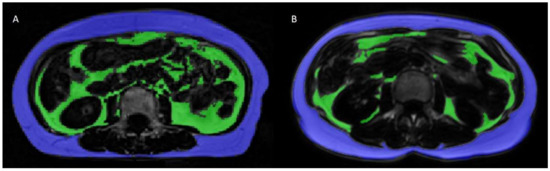

2.2. Adipose Tissue Volume Measurements

2.3. Calculation of SAT/VAT Volumes